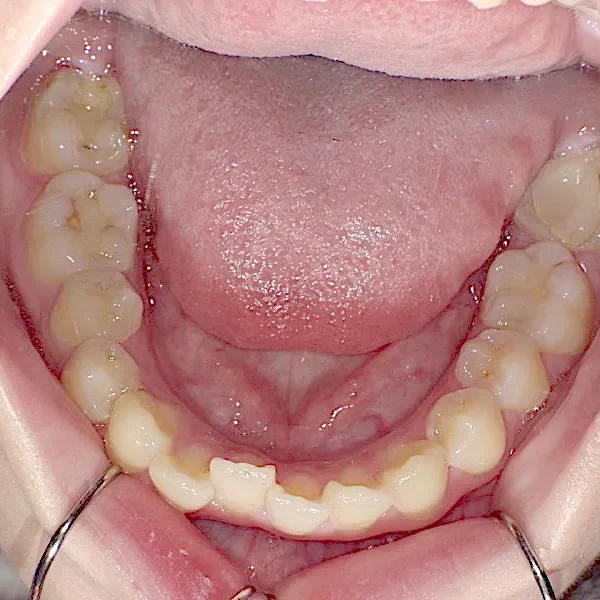

初診時

上下の歯並びがガタガタで口元が出ています。

元々小学生の時にマルチブラケット装置を上下につけ、矯正治療を受けていました。

何年か経過後、ガタガタと口元が気になると受診されました。

後戻りの原因は、リテーナーの装着時間不足、頬杖や、口呼吸などが考えられます。